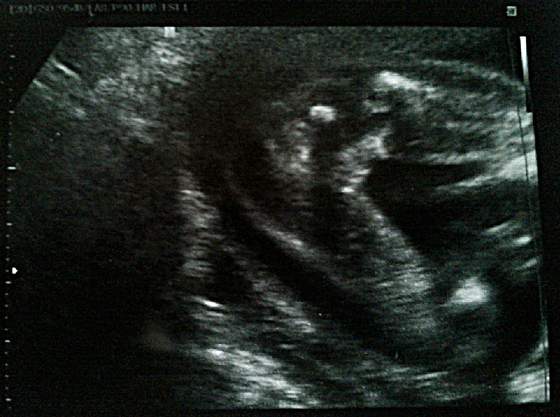

Yoanna - siusiak siusiak : D Dzidziunio śliczny